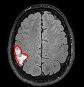

Automatic Segmentation of Brain Gliomas in Diffusion-Tensor

Magnetic Resonance Images

In

collaboration with the IRCCS San Raffaele

Hospital and Università Vita-Salute San Raffaele, Milan (Neuroradiology

Unit), we have developed a CAD system for the automatic or

semi-automatic detection of brain gliomas in magnetic resonance imaging

of different modality (T2W, FLAIR, DTI).